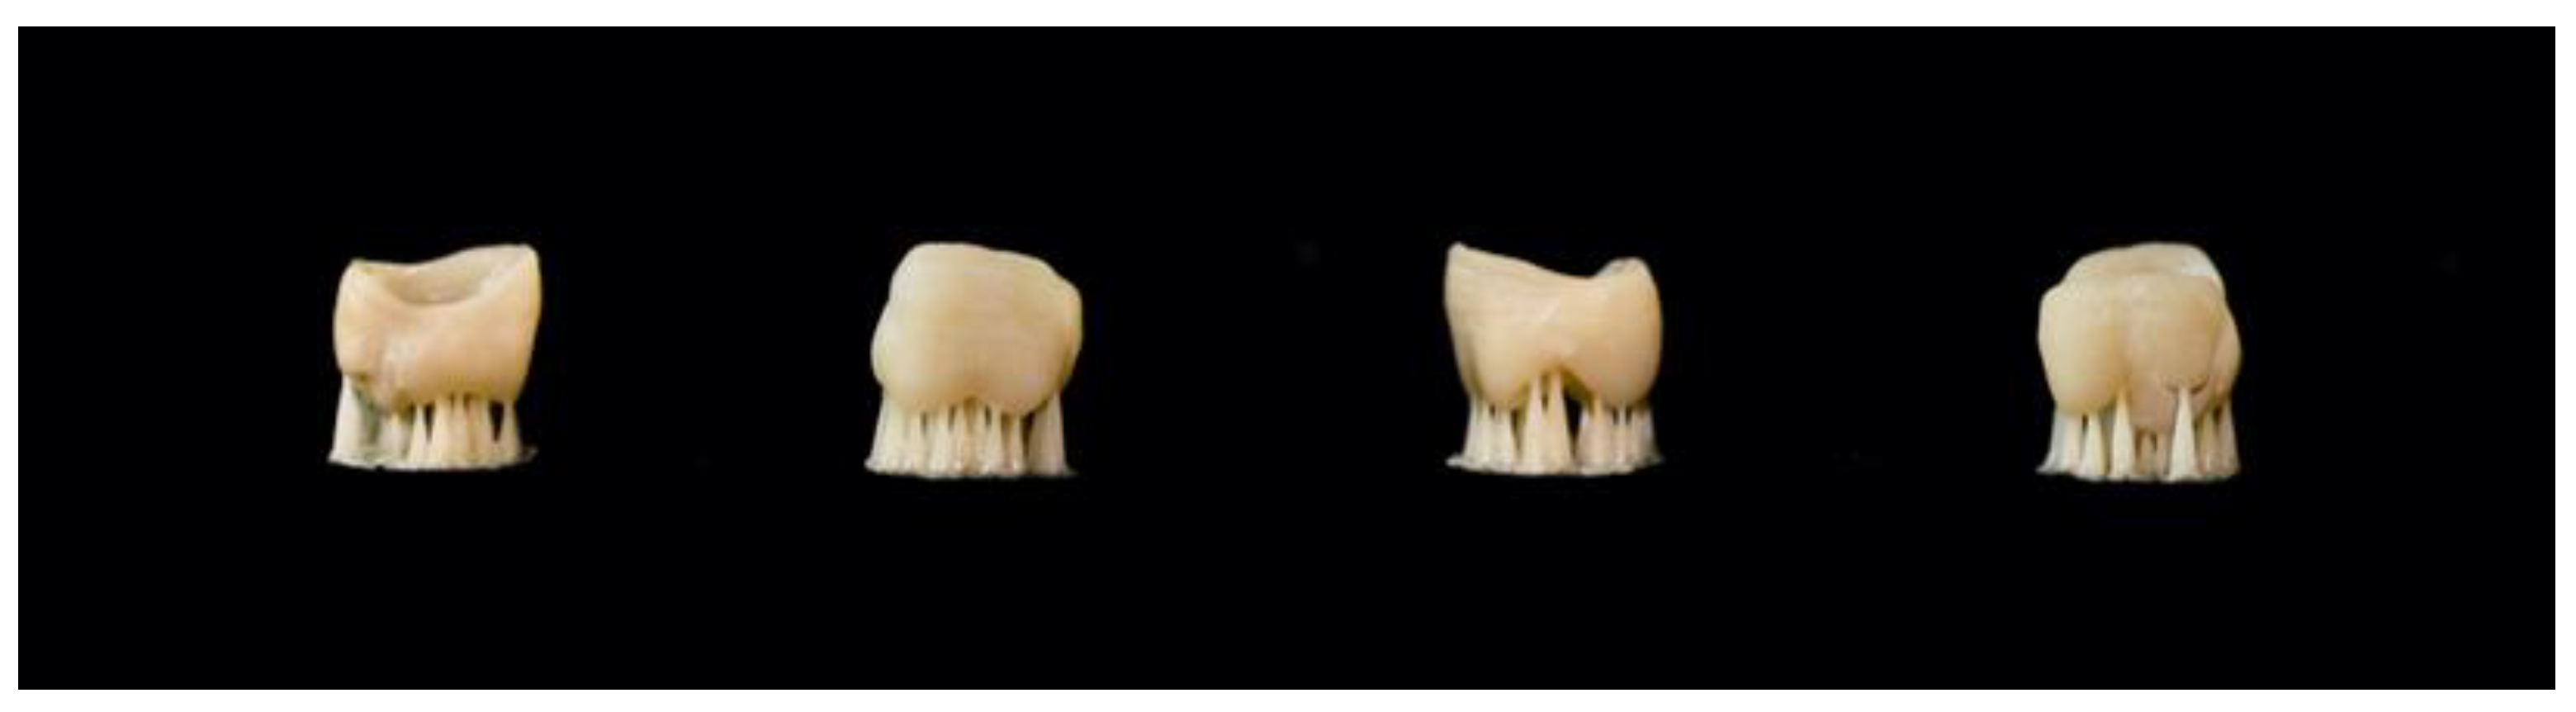

- Zimmermann, M.; Ender, A.; Egli, G.; Özcan, M.; Mehl, A. Fracture load of CAD/CAM-fabricated and 3D-printed composite crowns as a function of material thickness. Clin. Oral Investig. 2018, 23, 2777–2784. [Google Scholar] [CrossRef]

- Corbani, K.; Hardan, L.; Skienhe, H.; Özcan, M.; Alharbi, N.; Salameh, Z. Effect of material thickness on the fracture resistance and failure pattern of 3D-printed composite crowns. Int. J. Comput. Dent. 2020, 23, 225–233. [Google Scholar] [PubMed]

| Donmez & Okutan, 2022 [20] | Additive manufactured: 1. Crowntec (SP) Subtractive manufactured: 2. Brilliant Crios (BC) 3. Vita Enamic (VE) 4. Cerasmart 270 (CS) A total of n = 40 was measured. For each material n = 10. | 1. Saremco Dental AG 2. Coltène AG 3. Vita Zahnfabrik 4. GC Corporation | For definitive restorations | Digital light processing-based 3D printer (MAX UV; ASIGA, Sydney, Australia) | Parameters were set to a thickness of 50 μm, exposure time of 1.8 s, maximum light intensity of 12.14 mW/cm2, z compensation of 0 μm, and xy compensation of 0 μm. Following the printing process, the external surfaces of the crowns were cleaned with an alcohol-soaked (96%) cloth, while the internal surfaces were cleaned with a brush soaked in an alcohol solution until all resin residues were completely removed. Then, crowns were dried by using an air syringe and were light cured with 4000 lighting exposures by using a Xenon lamp-curing device (Otoflash G171; NK Optik, Baierbrunn, Germany) under nitrogen oxide gas atmosphere. | Marginal gap Fracture resistance (maximum load to failure in N) | Full contour maxillary first pre-molar crown. The height of the crown was 9 mm from the buccal aspect and 8.5 mm from the palatal aspect, while the thickness of the restoration was 2 mm in the proximal surfaces, 2.5 mm in the buccal and palatal surfaces, and the minimum occlusal thickness was 1.5 mm. The cement gap used was 25 μm, while the extra cement gap (cement spacer) was set to 50 μm. | Material type did not affect fracture resistance values (p = 0.209). Implant-supported 3D-printed composite crowns showed higher marginal adaptation compared with the milled crowns before and after cementation. In addition, all crowns endured similar forces before fracture. |

| Suksuphan et al., 2023 [24] | Additive manufactured: 1. Varseosmile (VS) Subtractive manufactured: 2. Cerasmart (CE) (hybrid nanoceramic) 3. Vita Enamic (VE) (polymer-infiltrated ceramic network (PICN)) A total of n = 90 was measured. For each material (n = 30) three different occlusal thicknesses were made n = 10 for 0.8 mm, n = 10 for 1.0 mm and n = 10 for 1.5 mm. | 1. Bego 2. GC Corporation 3. Vita Zahnfabrik | For definitive restorations | DLP based printer, FreeForm Pro 2 (ASIGA; Anaheim Hills, CA, USA) | Post-cured to the manufacturer’s recommendations. All crowns were cleaned with ultrasonic baths, air-dried. | Marginal adaptation Fracture resistance | A mandibular first molar based on the preparation guidelines for full ceramic crowns (1.0 mm occlusal reduction, 1.2 mm proximal, axial reduction with 6 degrees of convergence profile, 0.8 mm deep chamfer crown margin, and round line angles). Cement spacer was set to 50 μm. Single-molar crowns with occlusal thicknesses of 0.8, 1, and 1.5 mm. | For all occlusal thicknesses, the vs. crowns demonstrated the lowest AMD and MG distances, significantly different from those of the other two milling groups (p < 0.05), whereas CE and VE did not differ significantly (p > 0.05). All vs. crowns were fractured using the lowest loading forces (1480.3 ± 226.1 to 1747.2 ± 108.7 N). No CE and 1 and 1.5 mm VE crowns fractured under a 2000 N maximum load. All hybrid-material crowns demonstrated favorable marginal adaptation within a clinically acceptable range, with 3D printing yielding superior results to milling. All materials could withstand normal occlusal force even with a 0.8 mm occlusal thickness. |

| Zimmermann et al., 2018 [14] | Additive manufactured: 1. els-3D (3D-printed composite) (3D) Subtractive manufactured (particle filled composites): 2. Lava Ultimate (LU) 3. Cerasmart (CE) 4. Brilliant Crios (BC) Control groups: 5. Vita Enamic, hybrid ceramic (VE) 6. e.max CAD, lithium disilicate ceramic (EC) A total of n = 180 was measured. For each material (n = 30), three different occlusal thicknesses were made n = 10 for 0.5 mm, n = 10 for 1.0 mm and n = 10 for 1.5 mm. | 1. Saremco Dental AG 2. 3M ESPE 3. GC Corporation 4. Coltène AG 5. Vita Zahnfabrik 6. Ivoclar Vivadent AG | For definitive restorations | DLP 3D printing device (Freeform Pro 2, ASIGA; Anaheim Hills, CA, USA) | The spacer parameter was set to 80 μm. Parameters were set to slice thickness 50 μm, exposure time 0.6 s, minimum/maximum light intensity 13.14 mW/cm2, z compensation 0 μm, xy compensation 0 μm. Crowns of group 3D were first cleaned and washed in isopropanol 98% for 2 × 3 min using ultrasonic and then light cured with 4000 lighting exposures using Otoflash G171 device under nitrogen oxide gas atmosphere. | Fatigue Fracture load | Single molar crown | All particle-filled composite crowns with 0.5 mm thickness survived fatigue testing. The maximum fracture loading forces significantly varied among the groups tested. There was a statistically significant two-way interaction between material and thickness, p = 0.003. |